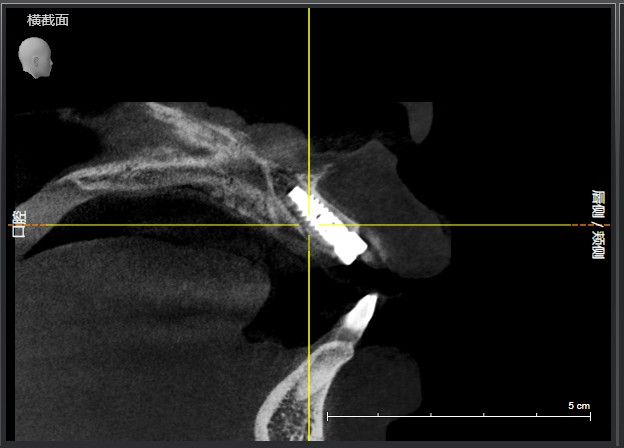

患者右上中切牙外伤导致冠根折,腭侧折面至骨下2mm,需要拔除患牙,x片显示唇腭侧牙槽骨完整,唇侧牙槽骨厚度1.5mm,根尖区剩余牙槽骨也有8mm,符合即拔即种即修复基本条件,患者知情同意下,术前两小时CEREC数字化扫描,设计种植导板,术前准备,拔除患牙,种植导板精密就位,种植窝完成制备,植入植体,拔牙窝间隙中植入Bio-oss骨粉,放置扫描杆,CEREC数字化扫描,一小时后即有一颗和左侧中切牙形态,颜色一致的右侧中切牙,不需要缝合,术后无疼痛,患者非常满意,CEREC数字化技术带给你无限可能!